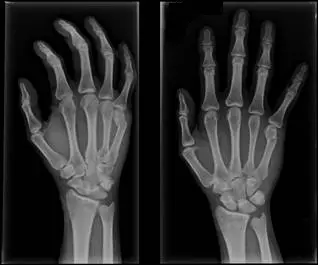

27 歲男性病人發生車禍造成右手疼痛,手部 X光片如附圖,最正確的診斷為?

本題附圖為右手的 X 光影像,包含**正位(PA view)及斜位(oblique view)**兩張。

- 骨折位置:在**第五掌骨頸部(neck of the 5th metacarpal)**可見明顯骨折線,骨折線呈橫向,位於第五掌骨頭(metacarpal head)近端

- 骨折型態:遠端骨折片(distal fragment,即掌骨頭)呈現掌側(volar)移位/彎曲(volar angulation),這是 boxer's fracture 的典型特徵

- 第五指掌指關節(MCP joint):因骨折片向掌側彎曲,正位片可見第五指「握拳時指節消失」(loss of knuckle)的影像

- 其他掌骨:第一至第四掌骨結構完整,無明顯骨折線

- 腕關節:橈骨、尺骨遠端及腕骨無異常,可排除 Colles 骨折相關的橈骨遠端骨折

此影像典型呈現第五掌骨頸骨折伴掌側彎曲,為 boxer's fracture 的